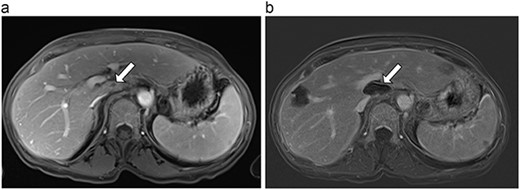

(a) Pre-ablation MRI demonstrating 15 mm lesion in caudate lobe of liver (image degraded by motion artifact). (b) Post-ablation MRI (20 days postoperatively) demonstrating 35 mm complete ablation of caudate lesion (image degraded by motion artifact).

| 2 (4a,b) | 67, M | Colon adenocarcinoma | 8 cycles capecitabine and oxaliplatin | 6 | Laparoscopic microwave ablation | 15 | 35 | 20 | 6 | No |